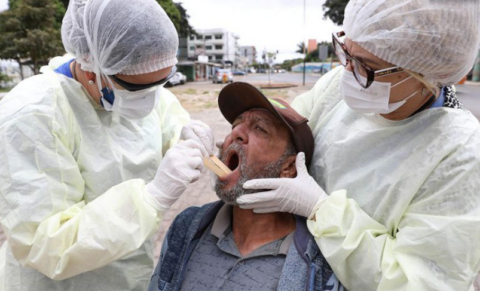

Novo boletim InfoGripe da Fiocruz aponta crescimento dos casos de Síndrome Respiratória Aguda Grave (SRAG)